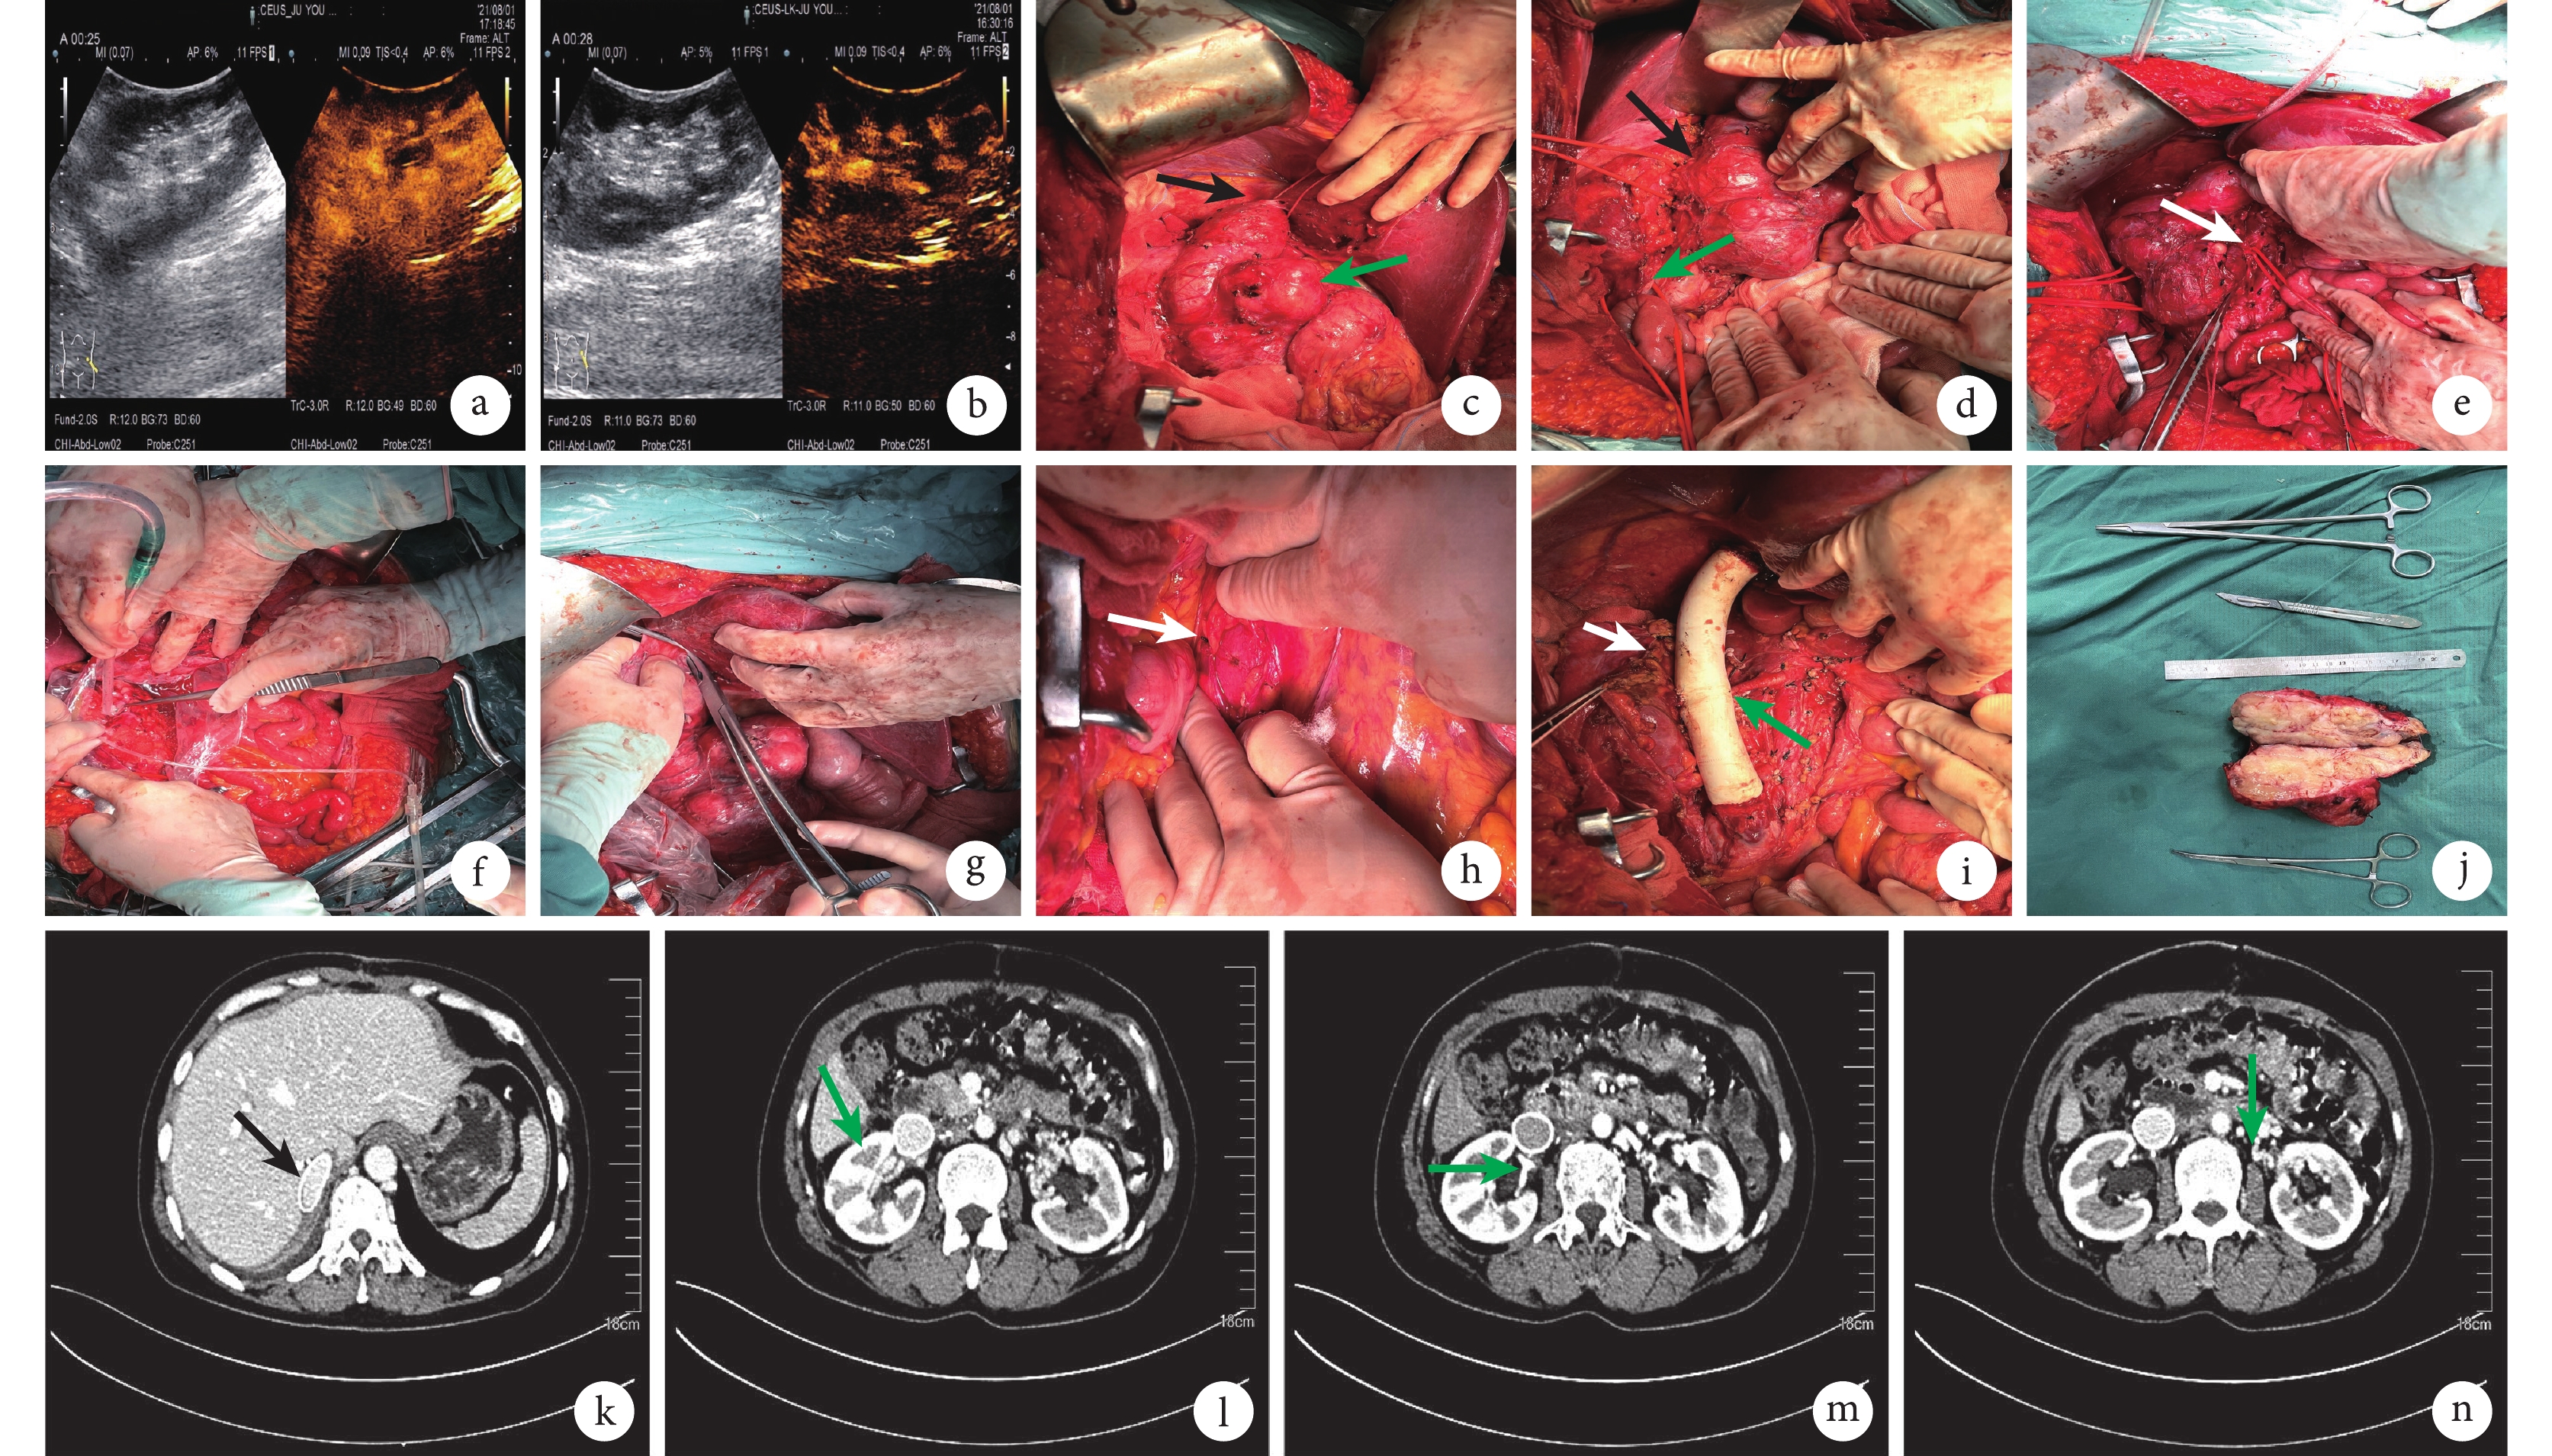

患者取仰臥位,全身麻醉后取腹正中切口聯合右側中腹部橫切口,充分暴露病灶。術中超聲探查可見IVC內及左、右腎靜脈內血栓形成,阻斷左側腎靜脈前后,行超聲探查及術中超聲造影檢查,前后對比未見明顯血流及阻力指數變化(圖2a和2b)。

a和 b:示左腎靜脈阻斷前(a)和阻斷后(b)的超聲造影檢查,未見明顯血流及阻力指數變化;c:解剖、懸吊第二肝門下方的IVC(黑箭),腫瘤包裹IVC(綠箭);d:分離及懸吊腎門(黑箭)及遠端IVC(綠箭);e:分離、懸吊左腎靜脈(白箭);f:UW液灌注右腎動脈,取凈右腎靜脈內的栓子;g:結扎第二肝門下方的IVC;h:結扎的左腎靜脈(白箭);i:右腎靜脈吻合于重建的IVC(白箭)與重建的右腎動脈(綠箭);j:完整剝除的腫瘤標本;k:術后人工血管管腔通暢(黑箭),未見血栓形成;l:重建的右腎靜脈管腔通暢(綠箭),未見流出道梗阻表現;m:重建的右腎動脈(綠箭);n:左腎靜脈切除后及其廣泛的側支循環(綠箭)

2.2 IVC切除重建與原位自體腎移植

分別于IVC機化血栓上方和雙側腎靜脈平面下方懸吊IVC(圖2c和2d),術中探查右腎靜脈主干內有機化血栓形成,分離左側腎靜脈(圖2e)。門靜脈阻斷鉗阻斷右側輸尿管,離斷右腎動脈及靜脈,取凈右側腎靜脈內機化血栓,自右側腎動脈灌注UW液,低溫保護右側腎臟(圖2f)。自IVC機化血栓遠端離斷IVC(圖2g),并于左腎靜脈栓子遠端離斷左側腎靜脈(圖2h),斷端縫扎,完整切除腫瘤。予以人工血管(D:22 mm;L:20 cm)橋接IVC,3-0血管線連續縫合;并用7-0血管線吻合右側腎動脈,將右側腎靜脈與人工血管行端-側吻合,開放后予以快速右腎復溫,可見腎臟顏色紅潤,原位固定右腎(圖2i)。圖2j示完整剝除的腫瘤標本。

2.3 血管重建后超聲(造影)檢查

患者出院后規律口服利伐沙班片抗凝治療,至投稿時已隨訪4個月,患者一般情況良好,復查腹部增強CT(圖2k~2n),見人工血管及腎動靜脈管腔通暢,未見狹窄及血栓形成,腹部無新發占位性病變。